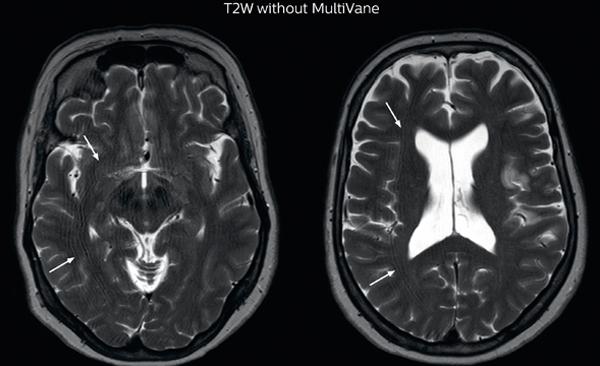

“MultiVane XD is especially useful for imaging patients with diseases that cause white matter changes on T2-weighted images”

“Motion artifacts can obscure subtle findings, make image interpretation more difficult and decrease diagnosis confidence. For example, when imaging the cerebellum or brain stem, or when looking for subtle multiple sclerosis (MS) lesions, motion can be problematic,” says Dr Nickerson. MultiVane XD motion-free imaging delivers diagnostic images even in the case of severe patient motion. A more relevant patient group is one with typical small artifacts related to moderate motion like an occasional cough. The absence of those artefacts brings forth better day-to-day diagnostic confidence. MultiVane XD works in multiple orientations and for various contrasts, such as T1-weighted, T2 weighted and FLAIR. Trevor Andrews, PhD, explains that the team compared motion artifacts seen in the brain with MultiVane XD and with T2-weighted TSE. “In nine out of the ten datasets in our studywe saw clear improvementswith MultiVane XD, while in the tenth dataset image qualitywas comparable. The MultiVane XD sequence is now used in the majority of patients that present at UVM for brain MRI.”

Motion-free imaging of white matter changes with MultiVane XD

“We saw MultiVane XD provide remarkable improvement, not only for artifacts caused by patient motion, but also for the extent of pulsation artifacts in the basal cisterns. Based on these results, we have added the MultiVane XD sequence to our brain studies,” says Dr. Nickerson. “MultiVane XD is especially useful when imaging patients with diseases that cause white matter changes on T2-weighted images, such as MS, small vessel disease, vasculitis and sarcoidosis,” says Dr. Nickerson. “Many of these are only visible on T2-weighted or FLAIR images, and sometimes aren’t even seen with FLAIR images. However, when using MultiVane XD and we don’t see any motion on the rest of the scan, but still do see a signal abnormality, we can probably attribute that to a real disease process, rather than an artifact.”

MRI motion artifact reduction in brain

The images made with MultiVane XD show significant reduction in motion artifact compared to the T2-weighted images without MultiVane below them. Scanned on Ingenia 3.0T